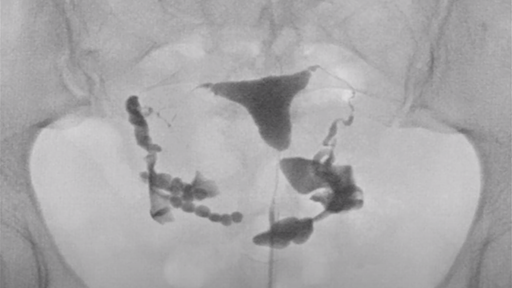

リピオドール®を使用した子宮卵管造影(HSG)の手順

提供: Dr. Kim Dreyer, Amsterdam University Medical Center (Netherlands)